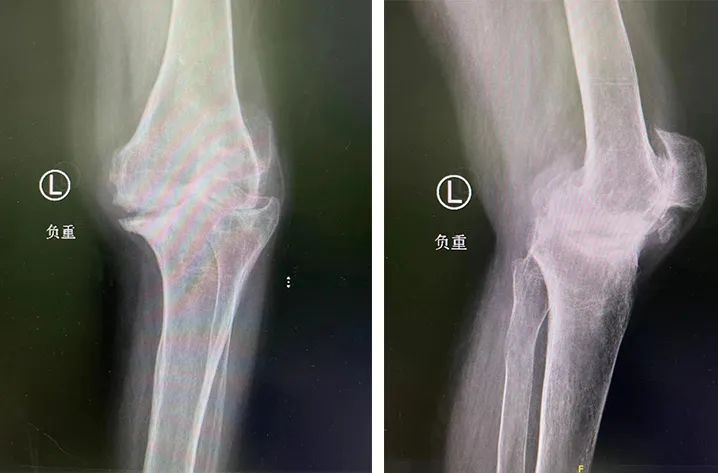

20 年前,李大姐双膝关节出现疼痛症状,尤其是在劳累后这种疼痛感更重,当时在当地医院被诊为类风湿性关节炎,之后的时间里她一直以药物控制。但在 10 年前,李大姐双膝关节疼痛等症状明显加重,每天早晨还会有双膝僵硬的情况,尤其是左膝,在行走或其他活动时受限明显,严重影响日常生活。

李大姐来到徐州仁慈医院关节外科,经过相关系统检查后,确诊为类风湿性关节炎及双膝骨性关节病 (KL 分级 IV 级)。